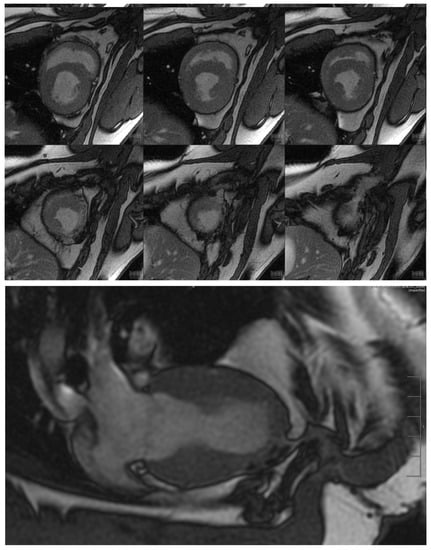

Figure 6. Cardio MRI three months following the reconstruction of the myocardium with an autologous vascularised gastric patch and stabilisation with a degradable magnesium scaffold. Top: Cine steady-state free precession (SSFP) in short axis from midventricular to apex cordis. Bottom: Cine SSFP with left ventricular two-chamber view. Good integration of the transplanted gastric patch.

Figure 7. Cardio MRI with delayed enhancement imaging 6 months following the reconstruction of the myocardium with an autologous vascularised gastric patch, and stabilisation with a degradable magnesium scaffold. Top: Four-chamber view with evidence of a significant ribbon-like late enhancement from apex cordis until the middle of the left ventricle, indicating fibrotic remodelling in the border zone between the myocardium and the transplanted gastric patch.

Before euthanasia, the test animals were examined by a cardiac MRI to determine the volume and functional data of the left ventricle. Stable integration of the stomach patch through adjacent scar tissue could be detected already after three months following implantation (Figure 6). The late enhancement of the contrast medium in this tissue area was a clear indication of fibrotic remodelling processes (Figure 7). All the animals without aneurysm formation showed normal left ventricular volume values as well as normal left ventricular ejection fractions. However, reduced motility of the ventricular wall in the junction area between the cardiac muscle and graft could be observed in all animals.

Three animals featured aneurysmal outpouching in varying degrees of severity in the area of the transplanted stomach tissue. The animal with the largest aneurysm in the area of the transplanted stomach tissue showed a significant increase in its end-diastolic and end-systolic volume, a significant reduction in stroke volume, and consecutively a significant decrease in the left ventricular ejection fraction to 36.4%. The animal that had developed the smallest aneurysm with a volume of only 6.8 mL showed no reduction in its left ventricular pump function (LV-EF 61.8%).